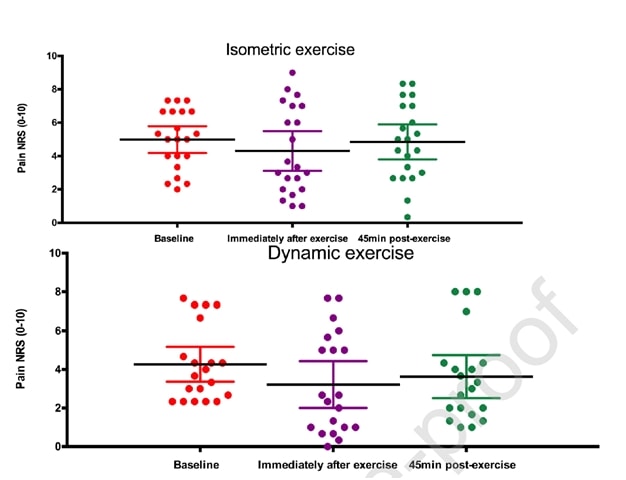

Río et al. (2015) iniciaron una pequeña tendencia cuando realizaron un ensayo cruzado en 6 jugadoras de voleibol con tendinopatía rotuliana. Sus resultados fueron sorprendentes, ya que todos los jugadores experimentaron una disminución inmediata del dolor, que pasó de una media de 7/10 en la escala NRS a 0, y sólo uno de los 6 informó de un dolor persistente de 1- durante al menos 45 minutos después de las contracciones isométricas. El protocolo que utilizaron fue de 5 series con 45 segundos de contracción en una máquina de extensión de piernas y un esfuerzo del 70% del esfuerzo voluntario máximo. También descubrieron que los isométricos eran capaces de disminuir la inhibición cortical y aumentar la fuerza en un 19%. Compararon la intervención isométrica con una intervención isotónica y los efectos observados en el grupo isométrico no pudieron conseguirse en el grupo isotónico:

Los mismos autores realizaron un estudio de seguimiento en temporada con atletas de salto dos años después (Rio et al. 2017) en el que compararon un programa isométrico y otro isotónico entre sí. En este estudio, los resultados fueron un poco más heterogéneos en ambos grupos, con una mayor disminución inmediata del dolor en el grupo isométrico:

Un estudio reciente de Holden et al. (2019) analizaron el efecto de los isométricos también en la tendinopatía rotuliana y no encontraron ningún efecto analgésico:

Figura de Holden et al. (2019)

Sin embargo, un alto porcentaje de mujeres y una edad media relativamente elevada no son típicos de la tendinopatía rotuliana, que suele ser una enfermedad de hombres jóvenes que saltan. Así que podría ser que el diagnóstico de tendinopatía rotuliana no fuera correcto en algunos casos. Ahora bien, aunque esos dos estudios se realizaron para la tendinopatía rotuliana, veamos si podemos transferir estos resultados a otros tendones.